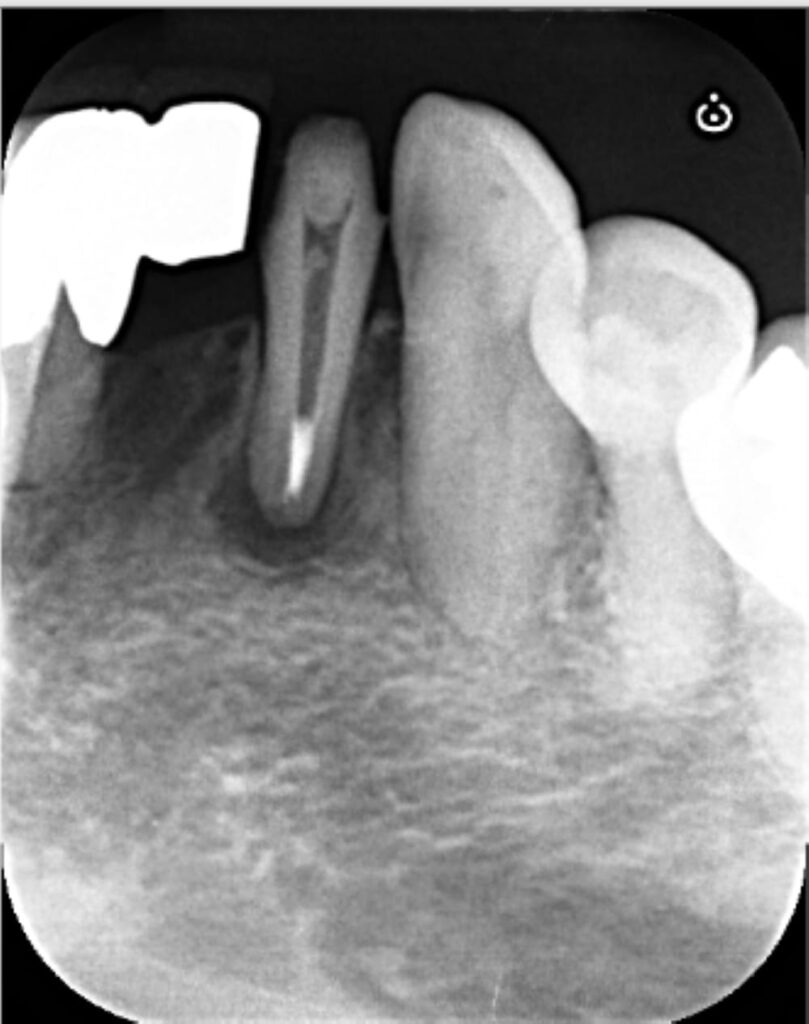

ステップ4

根管内を清掃すると、根の先端部分が大きく開いている状態でした。通常のガッタパーチャポイントを使用した根管充填では緊密な封鎖が困難なため、MTAセメントを使用して根尖部分を封鎖しました(写真は、MTAセメントを充填した直後)。

ステップ5

MTAセメント充填後、上部はガッタパーチャで封鎖し、その上部はレジンにて封鎖しました。前歯のため、経過観察期間中は仮歯で過ごしていただき、6ヶ月後のフォローアップを予定し終了となりました。